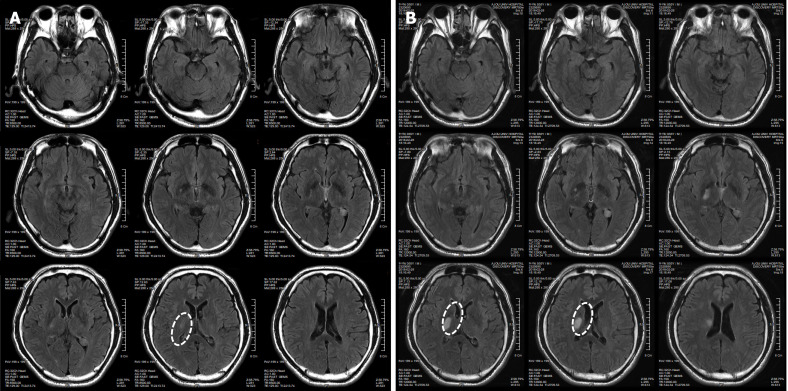

患者于2018年2月17日至18日出現(xiàn)暫時性無力癥狀,早上醒來后突發(fā)急性中風(fēng),導(dǎo)致左上肢和下肢癱瘓。患者在大學(xué)醫(yī)院急診室被診斷為Rt紋狀體囊性梗死(圖1A)。他于2018年3月2日出院,僅接受了阿司匹林處方,因為根據(jù)腦計算機斷層掃描 (CT) 掃描,他的腦血管正常,盡管他的病情在住院期間惡化(圖1)。出院當(dāng)天,他被送往康復(fù)專科醫(yī)院接受長期康復(fù)治療。然后他于2018年3月13日來韓國首爾生物美容與健康公司 (bBHC)-干細胞治療與研究所 (STRI)接受干細胞治療。